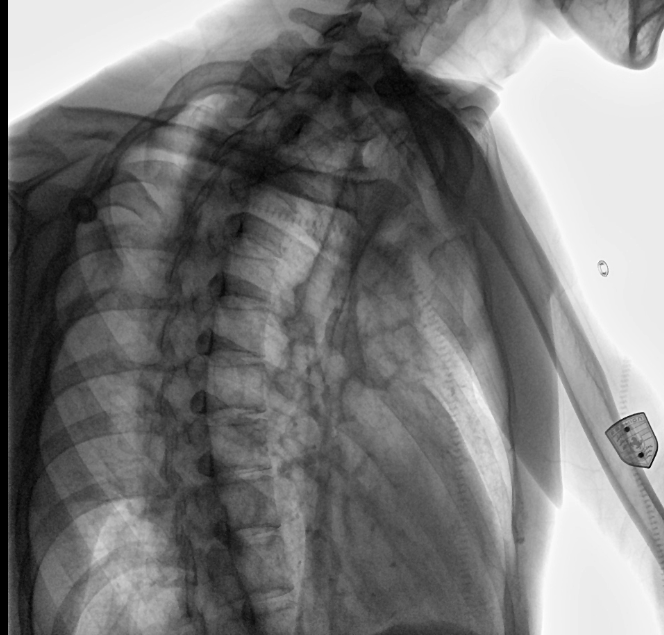

位于衡水市中醫(yī)醫(yī)院的動(dòng)態(tài)平板數(shù)字化X射線系統(tǒng)DTP571具備高速高清點(diǎn)片功能。這是一款對(duì)放射科十分友好的產(chǎn)品。因?yàn)樗迅咚俸透咔妩c(diǎn)片結(jié)合,既能方便影像技師有效地抓拍需要的病灶的影像,又能給予影像醫(yī)生清晰的影像進(jìn)行診斷。

衡水市中醫(yī)醫(yī)院的放射科主任醫(yī)師于金厚主任為患者進(jìn)行檢查

設(shè)備的穩(wěn)定性,表現(xiàn)性能方面,我院現(xiàn)在這臺(tái)動(dòng)態(tài)DR,一個(gè)上午能夠接待700-800名學(xué)生進(jìn)行體檢工作,如果是使用普通設(shè)備,包含體檢人員脫衣服,擺位置,達(dá)到體檢要求在內(nèi),最快檢查速度是2-3分鐘,但沒有透視功能,無法承載這么多的量,而且需要2位醫(yī)師輪換操作。

衡水市中醫(yī)醫(yī)院的放射科主任醫(yī)師于金厚主任操作國產(chǎn)DR設(shè)備

動(dòng)態(tài)觀察診斷,實(shí)時(shí)高清點(diǎn)片